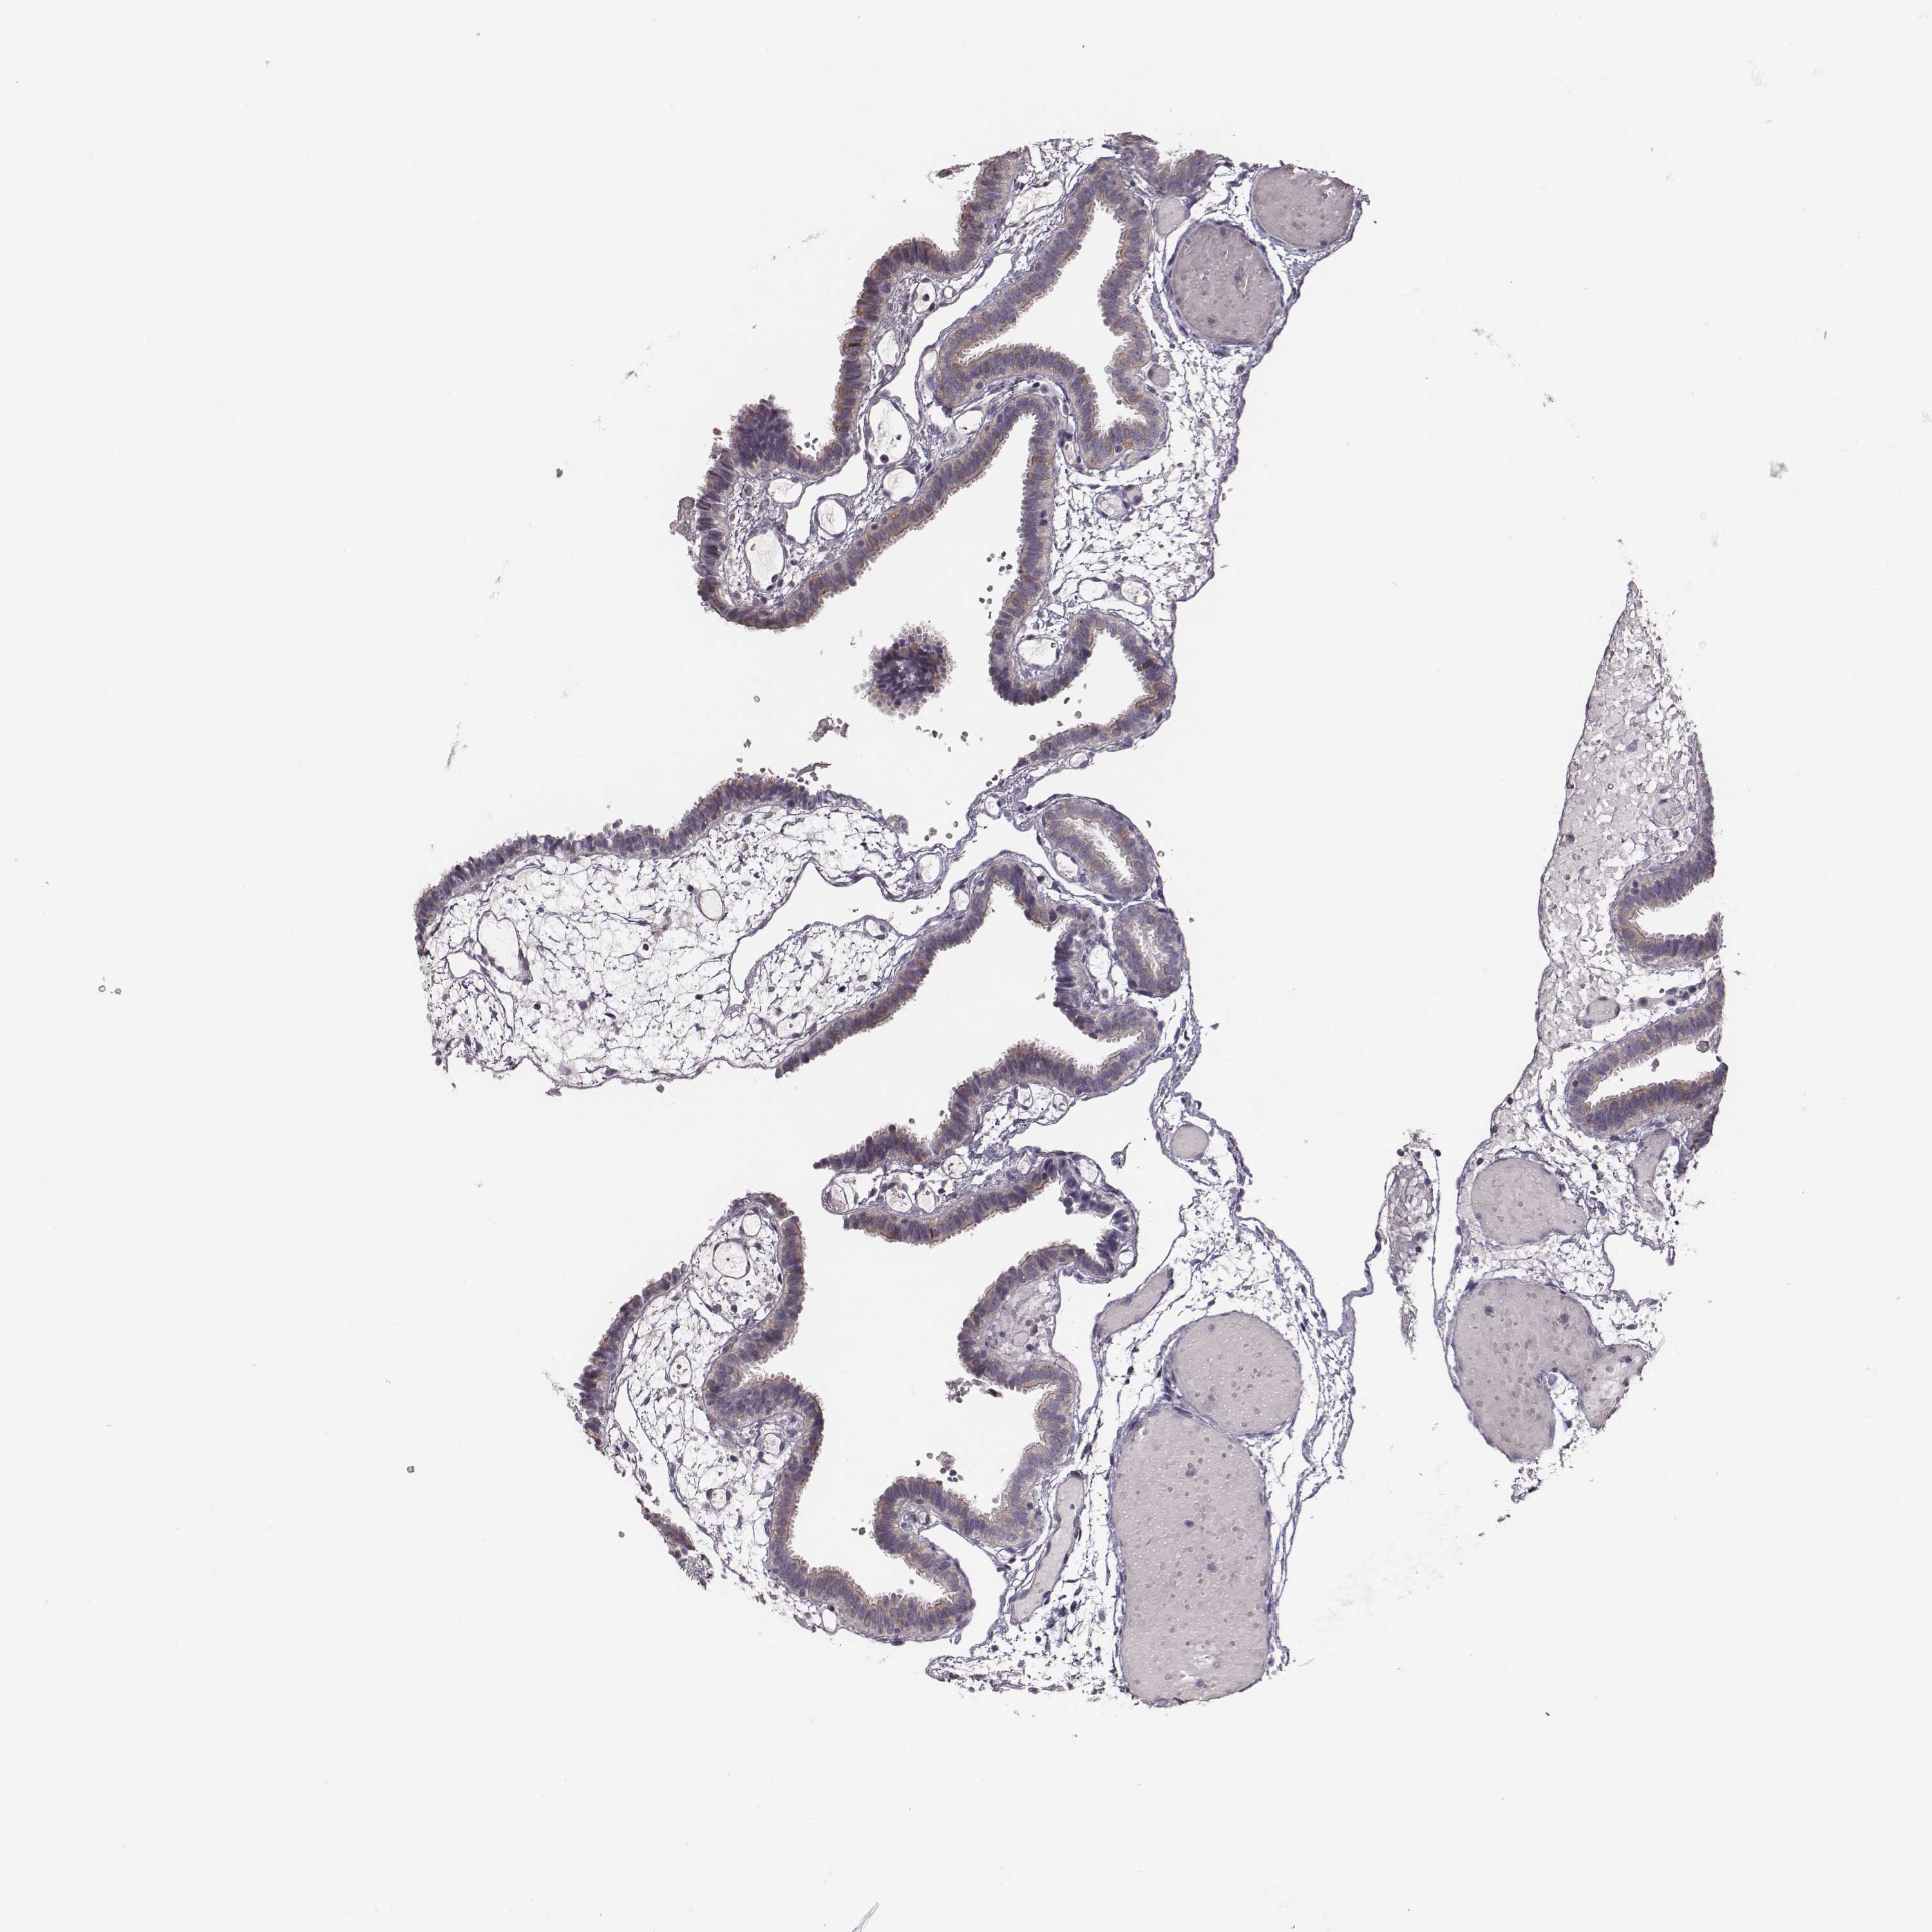

KAAG1